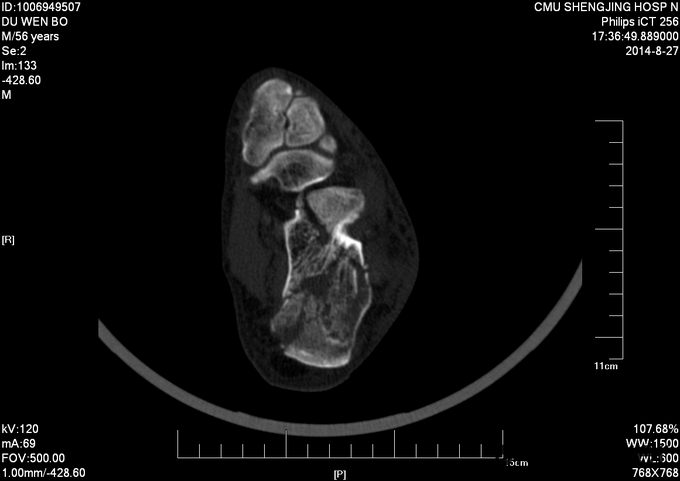

左跟骨骨折sanders2型

患者及其家属自述于2015-10-17 13:30 因在自家干活时不慎从2米高梯子上摔下,当时患者意识清醒,无法站立,左踝部疼痛、肿胀、活动受限,以“左踝部骨折”为诊断收入我科;患者伤来无发热、无头晕、恶心呕吐,无呼吸困难,既往饮食睡眠可,大小便正常; 左踝部肿胀明显,压痛阳性,左踝部活动受限,可闻及骨擦音及骨擦感;患肢皮肤感觉较健侧无明显异常,足趾可活动,足背动脉可触及;